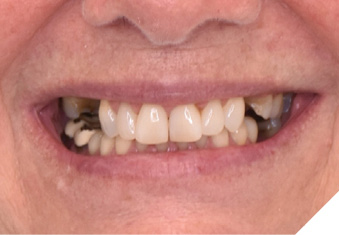

A 65-year-old woman comes to the office with the chief complaint of worn-down teeth, missing teeth, tooth sensitivity, especially on maxillary teeth and TMJ pain. Her past medical history was reviewed and was significant for asthma, insomnia, hypercholesterolemia, hypothyroidism, and anxiety disorder. She denied any sleep disturbances. Her medications included salbutamol, ezetimibe, quetiapine, and levothyroxine. She referred to being allergic to dust and shellfish and sensitive to propofol. She had a right mastectomy in 2014 due to breast cancer. No chemotherapy or radiation was done. Her diet was considered normal, and she denied any consumption of acidic drinks and denied any history of regurgitation. She denied any parafunctional habits during the day. She was using a maxillary transitional partial denture since she had lost some of her teeth due to fracture and caries. No other problems were evidenced. Intraoral exam showed moderate attrition lesions of posterior teeth, porcelain fused to metal crowns on teeth 46 and 47 had the porcelain portion worn down, exposing the metal substructure. Missing teeth included teeth 14,15,16,18,24,28, 36,38,48. Palatal surfaces of maxillary anterior teeth also appeared worn down. An abfraction lesion was found on tooth 23. No carious lesions were found in any of her teeth. Composite restorations on mandibular anterior teeth were chipped or were missing (Figs. 6-11) She also presented with limited mouth opening: 35 mm interincisal distance at maximum opening. There was bilateral pain on palpation of preauricular areas. Her pain was the worst early in the morning which suggested night parafunction. No crepitus, or joint clicking were found.

Fig. 9

Articulated diagnostic casts showed very limited to no overjet and 90% of overbite. The wear pattern on the palatal aspect of her maxillary teeth appeared to be secondary to her tight occlusion since mandibular anterior teeth were in close contact with these surfaces with no “room” for protrusive movements. The diagnosis for this patient was: partial edentulism, failing existing restorations and attrition and abfraction secondary to parafunction. We discussed different options, including orthodontics in order to increase her overjet so we could have prosthetic space to restore her worn down teeth. We also discussed tooth replacement options. After a second consultation appointment which she attended with her husband, she decided that she did not want to replace her teeth with removable prosthetics. She also declined referral to an orthodontist. After discussion of multiple options of treatment to address all her chief complaints, her treatment consisted of a full mouth reconstruction with full coverage restorations in Zirconia for teeth 11-13,17,22-23,25-27,32-42, 44-47 and partial coverage restorations with lithium disilicate restoration for teeth 33,34 and 43. Replacement of teeth was achieved with a fixed partial denture to replace tooth 36 and a 3-unit implant supported bridge to replace teeth 24-26. In terms of occlusion, we created a more favorable occlusion with a proper anterior guidance, canine disclusion with more freedom for protrusive movements, which hopefully would decrease the parafunction, and alleviate some of her muscle pain. Before completing the case, the patient spent several weeks with provisional restorations which reflected the increase in vertical dimension of occlusion and the new occlusal scheme. During this trial phase, we assessed comfort, esthetics, function, decrease in pain and speech (Figs. 12-17).